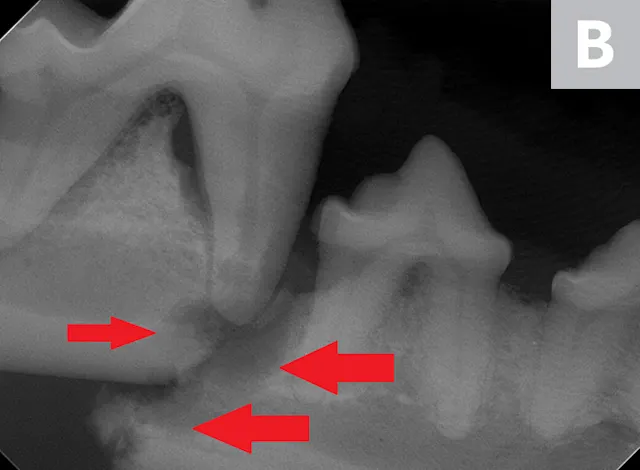

A complete oral examination confirmed stage 4 periodontal disease of numerous teeth (ie, first through fourth maxillary premolars, all maxillary molars, both maxillary canines, all remaining incisors). Dental radiographs confirmed bilateral mandibular fractures at the mesial root of the right mandibular first molar and distal root of the left mandibular first molar (Figures 1 and 2).

Preoperative intraoral dental radiographs of the right (A and B) and left (C) mandibular first molars. There is marked alveolar bone loss secondary to periodontal disease (blue lines), as well as pathologic, iatrogenic mandibular fractures (arrows).